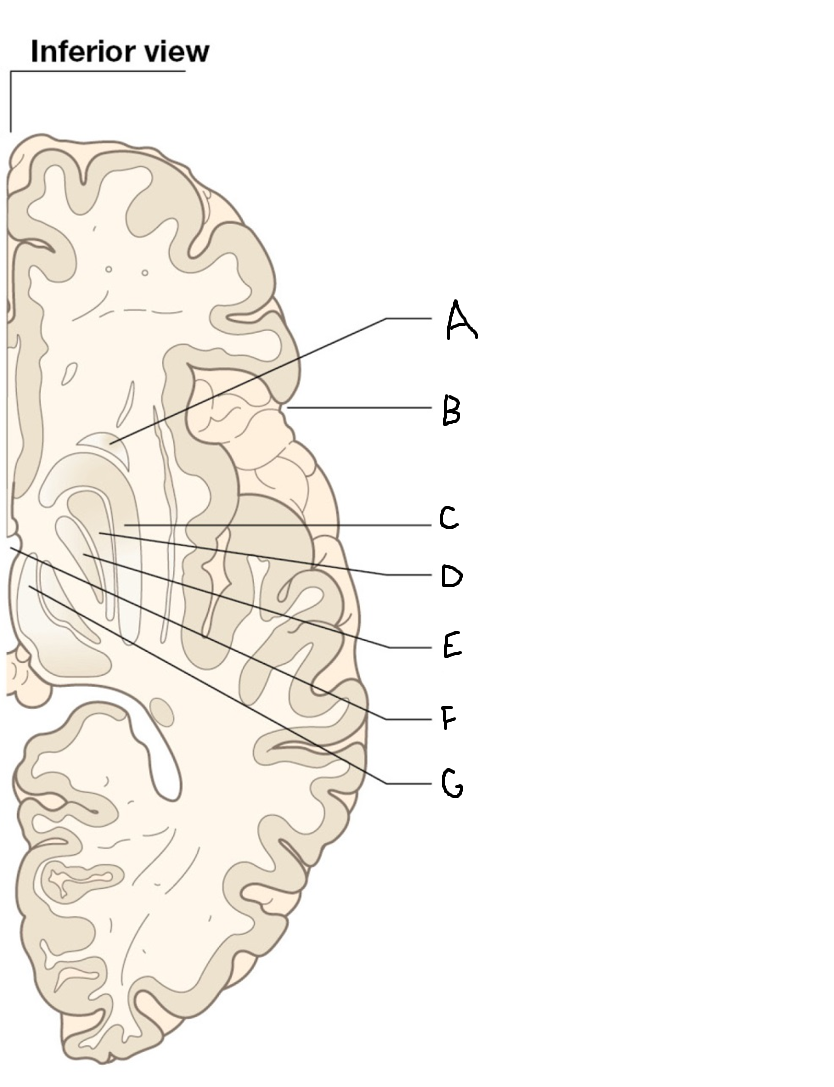

A

corpus callosum

B

lateral ventricle

C

internal capsule

D

third ventricle

E

tail of caudate nucleus

F

lateral ventricle

G

hippocampus

H

mammillary body

I

fornix

J

globus pallidus

K

putamen

L

caudate

M

thalamus

N